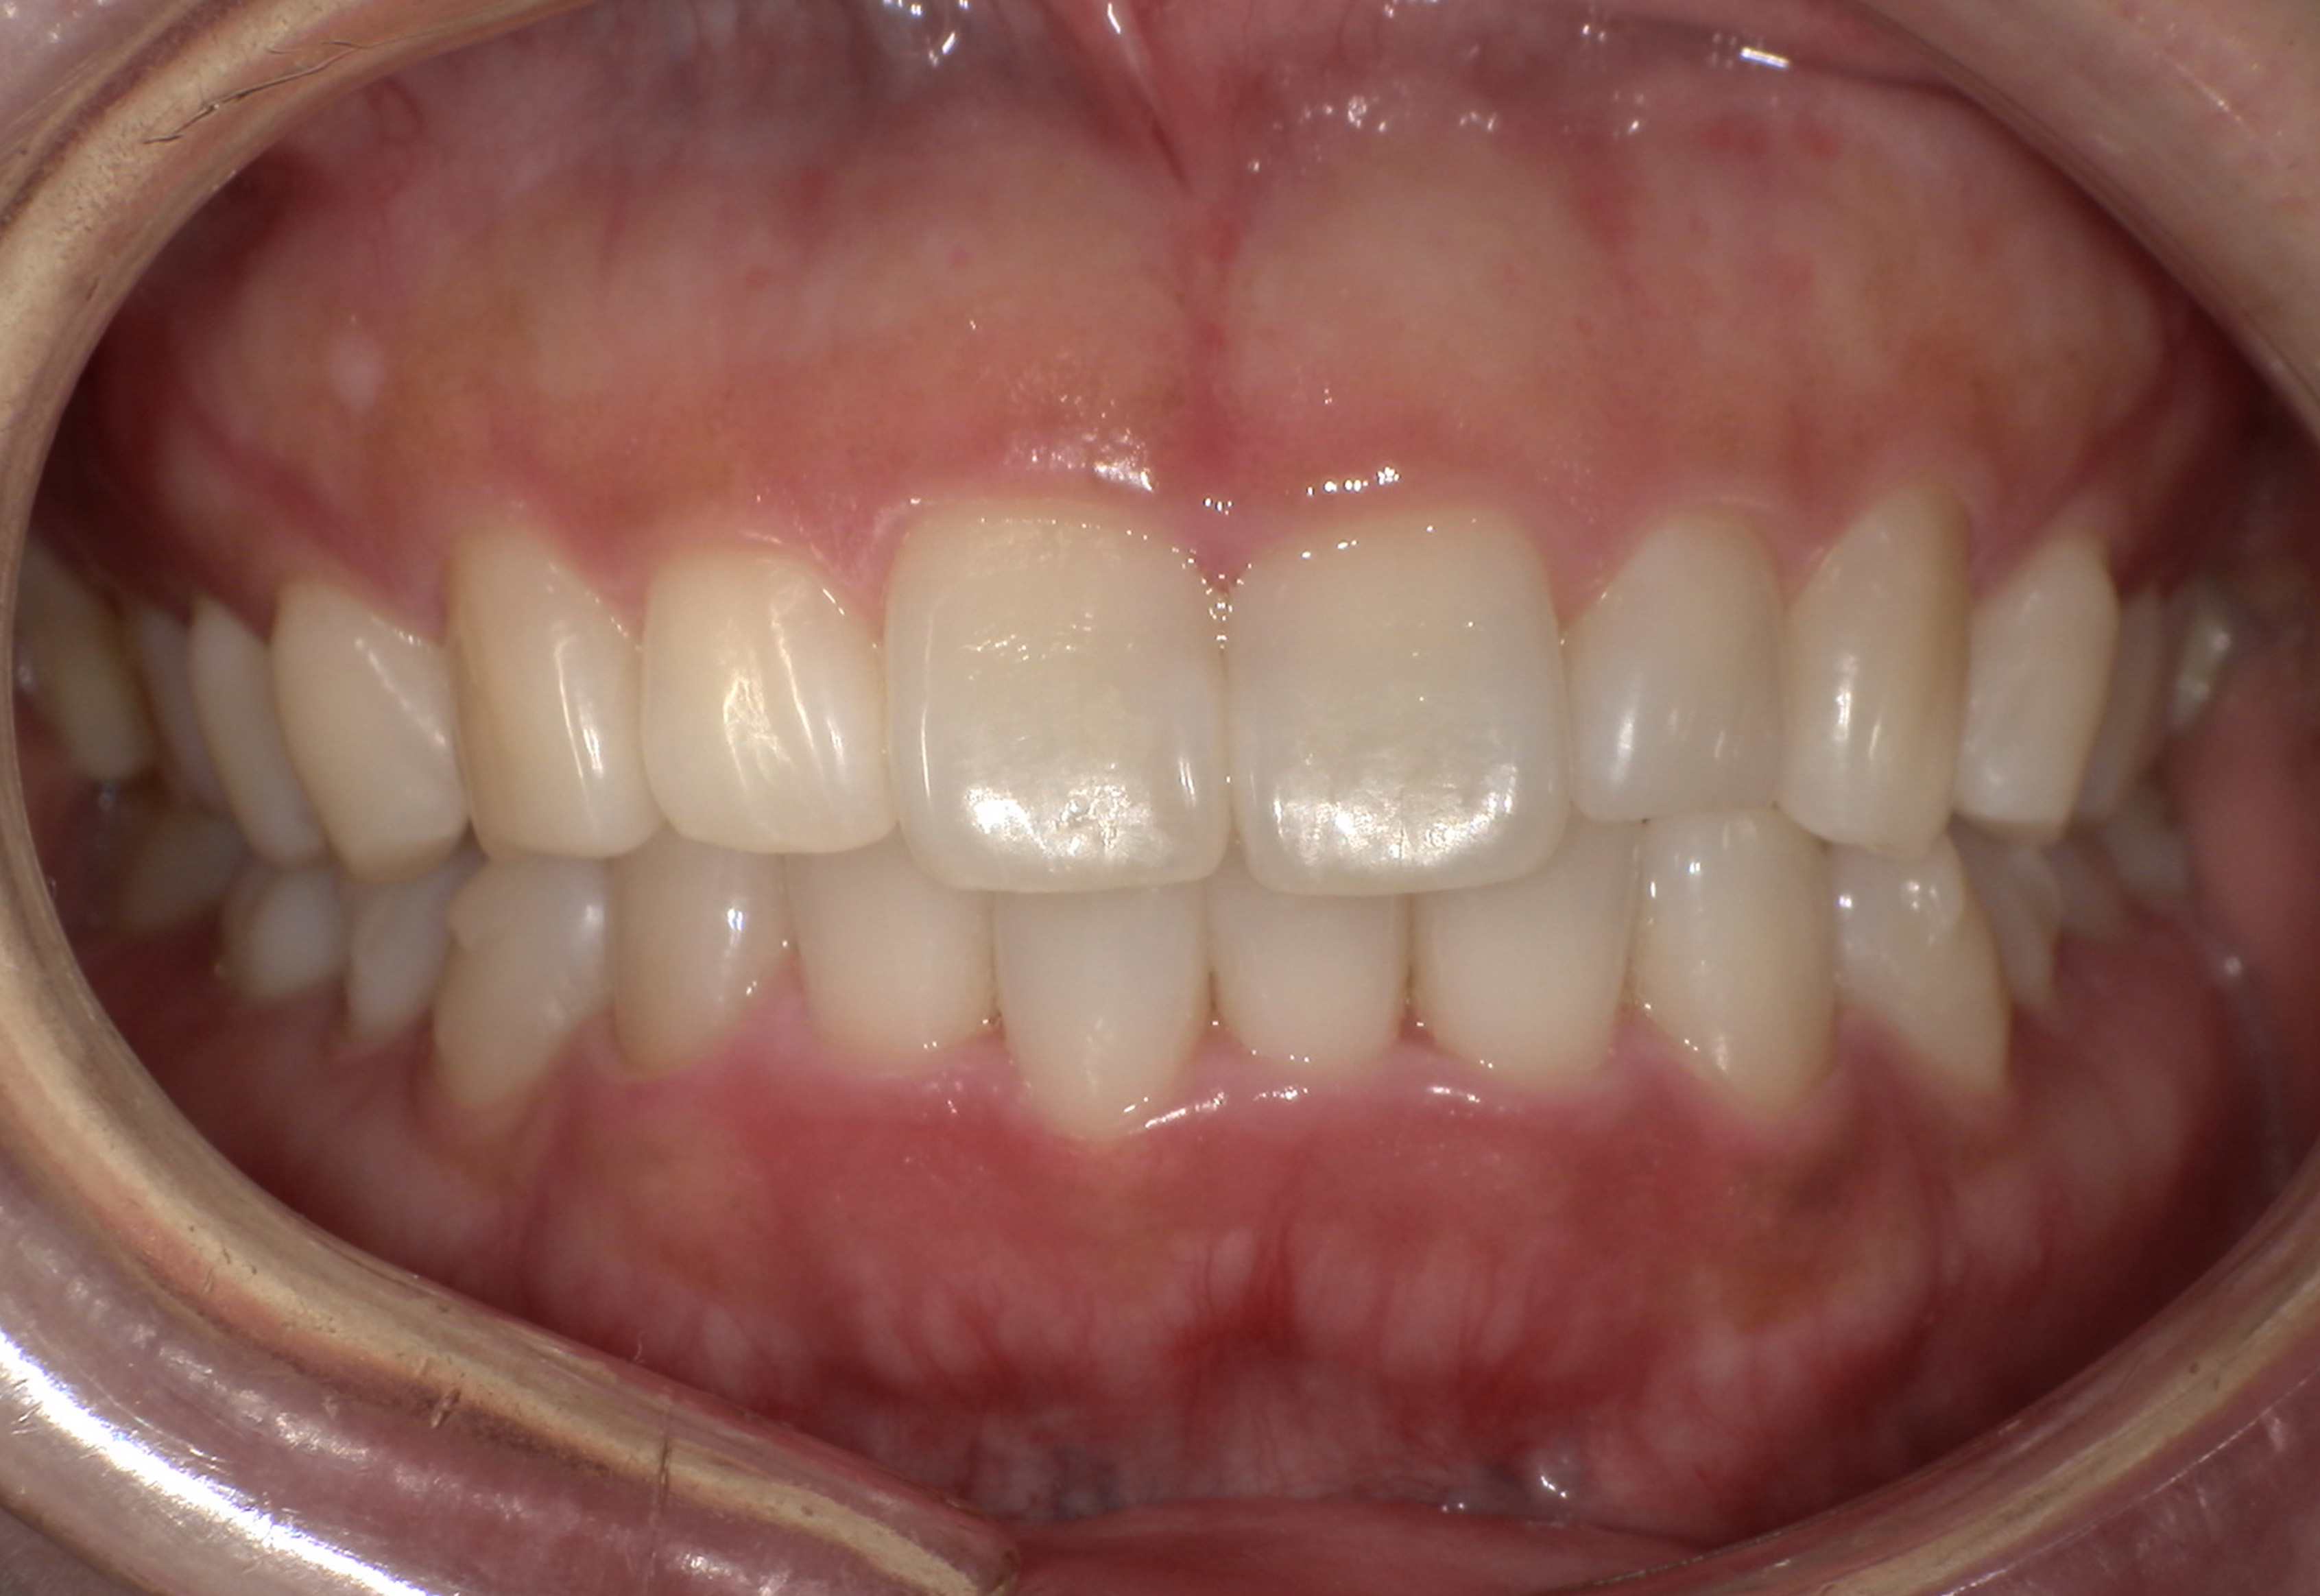

術前・術後の比較

| 術前 | 術後 |

|---|---|

![]() ![]() |

治療の経過を表示する

-

患者の方は親知らずの痛みがあり当院にお越しになりました。幼少期から歯医者が苦手で、痛みがあってもなかなか行く勇気がでなかったそうです。笑気鎮静法を併用しながら、右下の親知らずを抜歯しました。

2024.6.25パノラマレントゲン写真

親知らずの痛みがなくなった患者さんは、昔から歯並びが気になっていることを打ち明けてくれました。特に上の歯が少し前に出ていたり、隙間があったりしている点を治したいそうです。そこで、まず上の歯並びの矯正治療を開始しました。

最初のお口の中 ワイヤー装着して治療を開始

治療開始後3ヵ月経過すると、前歯の隙間や全体の乱れが減ってきました。口笛が吹けるようになったとのことです。

最初のお口の中 治療開始3ヵ月後

6ヵ月経過すると、矯正治療を終了し、前歯に被せ物の治療を行いました。

最初のお口の中 2025/3/22

被せ物装着

当院では、歯並びが気になる人に対して、矯正治療を行っています。また今回の症例のようにワイヤーを用いた治療からマウスピース矯正治療も行っておりますので、スタッフにお声かけください。

治療の概要

| 患者属性 | 30代男性、歯科恐怖症 |

| 主訴 | 上の前歯の歯並びを整えたい |

| 診断 | 歯列不正、う蝕歯 |

| 矯正装置 | 矯正ブラケットとワイヤー |

| 治療期間 | 約6ヵ月 |

| 通院回数 | 8回 |

| 治療費 | 矯正:基本料金(220,000円)+調整料(5,500円×6回)、補綴治療:72,600円、費用は税込 |

| 治療内容 | 上顎側切歯を2本抜歯した後、上顎の歯にブラケットを装着し、ワイヤー、矯正用ゴムで歯の移動を行いました。その後、被せ物の治療を行って治療を終了しています。 |

| リスクと副作用 | 矯正治療

補綴治療

|